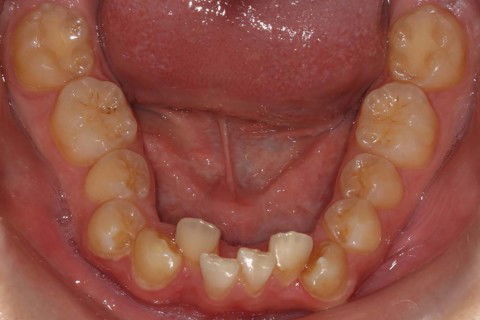

Inicial Ocl. Inf.

Paciente: Sexo masculino, 16 anos

Queixa principal: Apinhamento

Diagnóstico: Classe II, divisão 2

Sugestão de Tratamento: Tratamento ortodôntico com o uso do sistema de alinhadores removíveis Invisalign. Sem extrações dentarias, pois o perfil do paciente não era favorável. Por ser um paciente jovem, optou-se por uma expansão dentária controlada, buscando a remodelamento dos arcos.